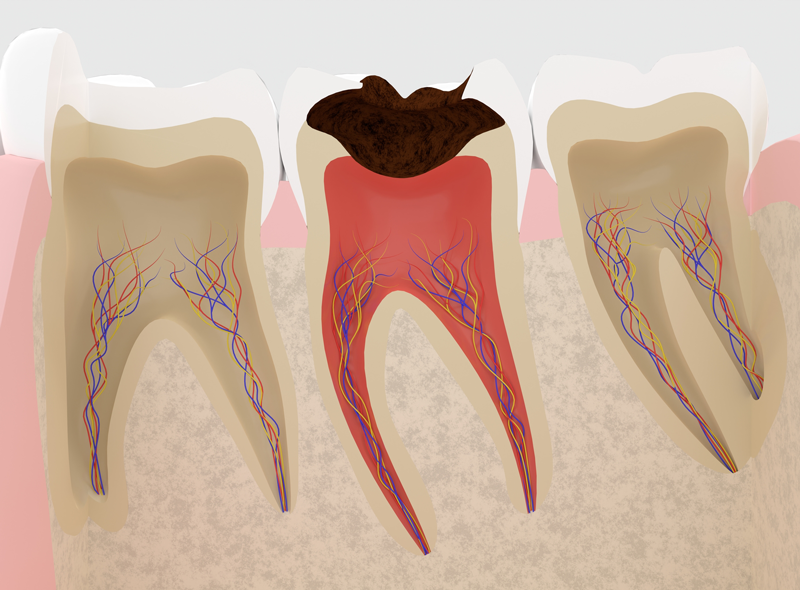

根管治療とは、一般に『歯の神経を抜く治療』『歯の根っこの治療』といわれる治療のことです。 私たちの歯の内側には、神経や血管を含む「歯髄(しずい)」と呼ばれる組織が存在しています。これらの神経や血管は「根管」と呼ばれる細い管を通って、全身の神経や血管へとつながっています。

大きな虫歯などでこの歯髄に細菌が感染した場合、歯髄全体を取り除き、根管内を清掃・消毒する治療をおこないます。これが皆さんが最初に受ける根管治療(神経を抜く治療)です。

再治療の原因になる「根尖病巣」

初回の根管治療がうまくいかないと、治療後も痛みや腫れを繰り返したり、歯の根っこの先に膿がたまる「根尖病巣(こんせんびょうそう)」を引き起こしたりします。このようなケースでは根管治療の再治療(歯の根っこの治療)をおこないますが、再治療が繰り返されるたびに歯へのダメージも大きくなり、最悪のケースでは抜歯にまで至ってしまいます。